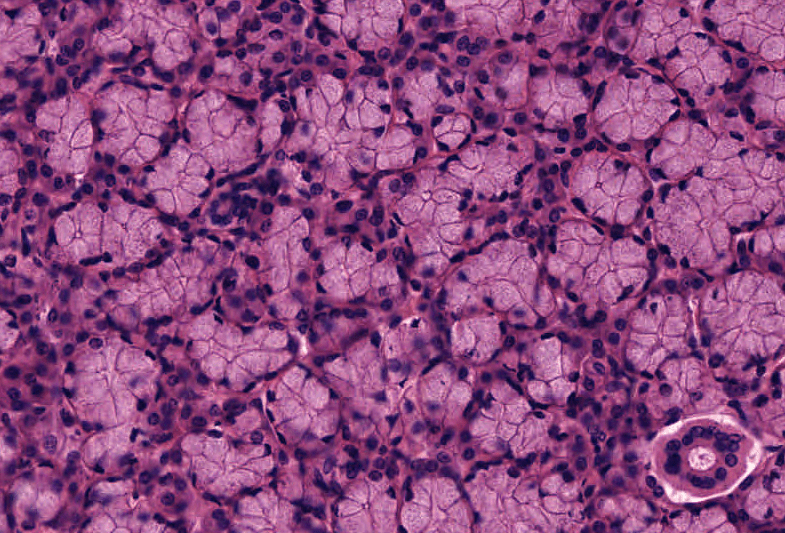

GLÁNDULA PARÓTIDA

Glándula salival mayor SEROSA y con adipocitos uniloculares.